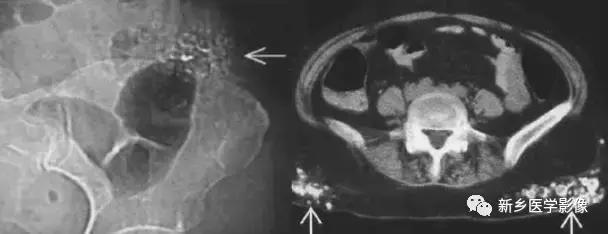

16、卵巢肿瘤畸胎瘤

常见的为畸胎瘤以及合并钙化的卵巢癌。